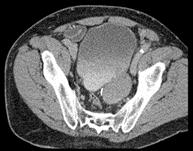

男,68岁,请根据所示图像,选择最可能诊断 ( )A、膀胱癌B、膀胱憩室C、先天性巨输尿管D、膀胱假性憩室E、输尿管囊肿

问题 男,68岁,请根据所示图像,选择最可能诊断 ( )

选项 A、膀胱癌 B、膀胱憩室 C、先天性巨输尿管 D、膀胱假性憩室 E、输尿管囊肿

答案 B